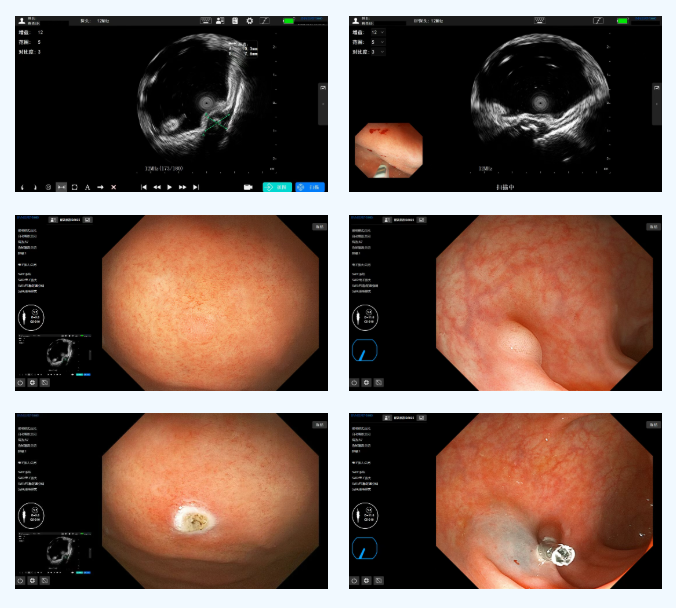

作为消化道疾病的核心诊疗技术,英美达高清胃肠镜系统集观察、诊断与治疗功能于一体。其高清晰度成像结合NSI窄带成像技术,能清晰呈现黏膜微血管与微腺管结构,为早期病变识别提供坚实基础。

联合其配套的超声小探头可在“直视”黏膜的基础上实现“透视”管壁的立体观察,令细微病变无处遁形,助力医生快速精准发现病灶,大幅提升消化道早癌及癌前病变诊断率,为患者带来更高治愈希望。